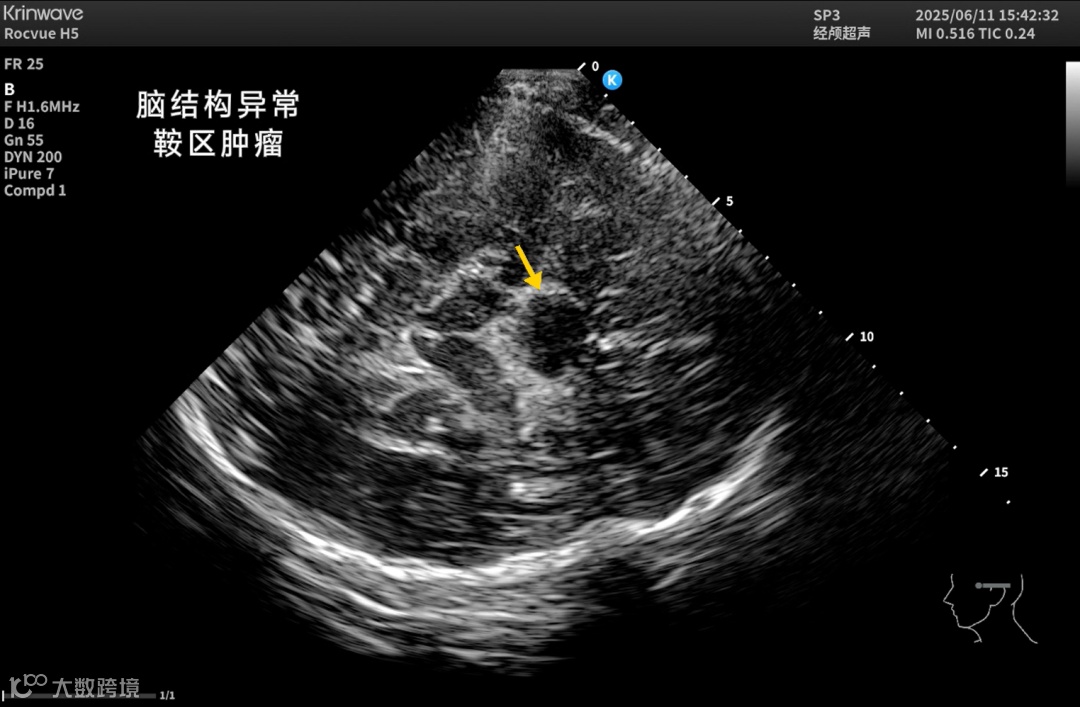

颅脑一直是超声成像的难题——

颅骨厚、衰减强、反射乱,声能传输率不足10%。

让超声在颅脑领域真正“看得见、看得清”。

● 神经疾病研究

结合kOS平台探索抑郁症、阿尔茨海默病等脑部疾病的影像学基础。